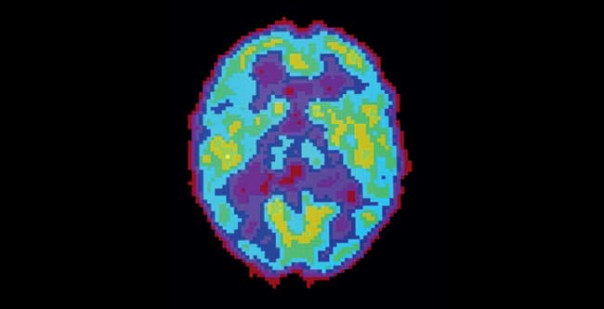

Активность мозга сильно различается не только во время бодрствования и сна — есть множество промежуточных состояний, которые можно различить во время позитронно-эмиссионной томографии.

ДЕПРИВАЦИЯ СНА. Активность мозга очень долго не спавшего человека снижена и похожа на стадию глубокого сна